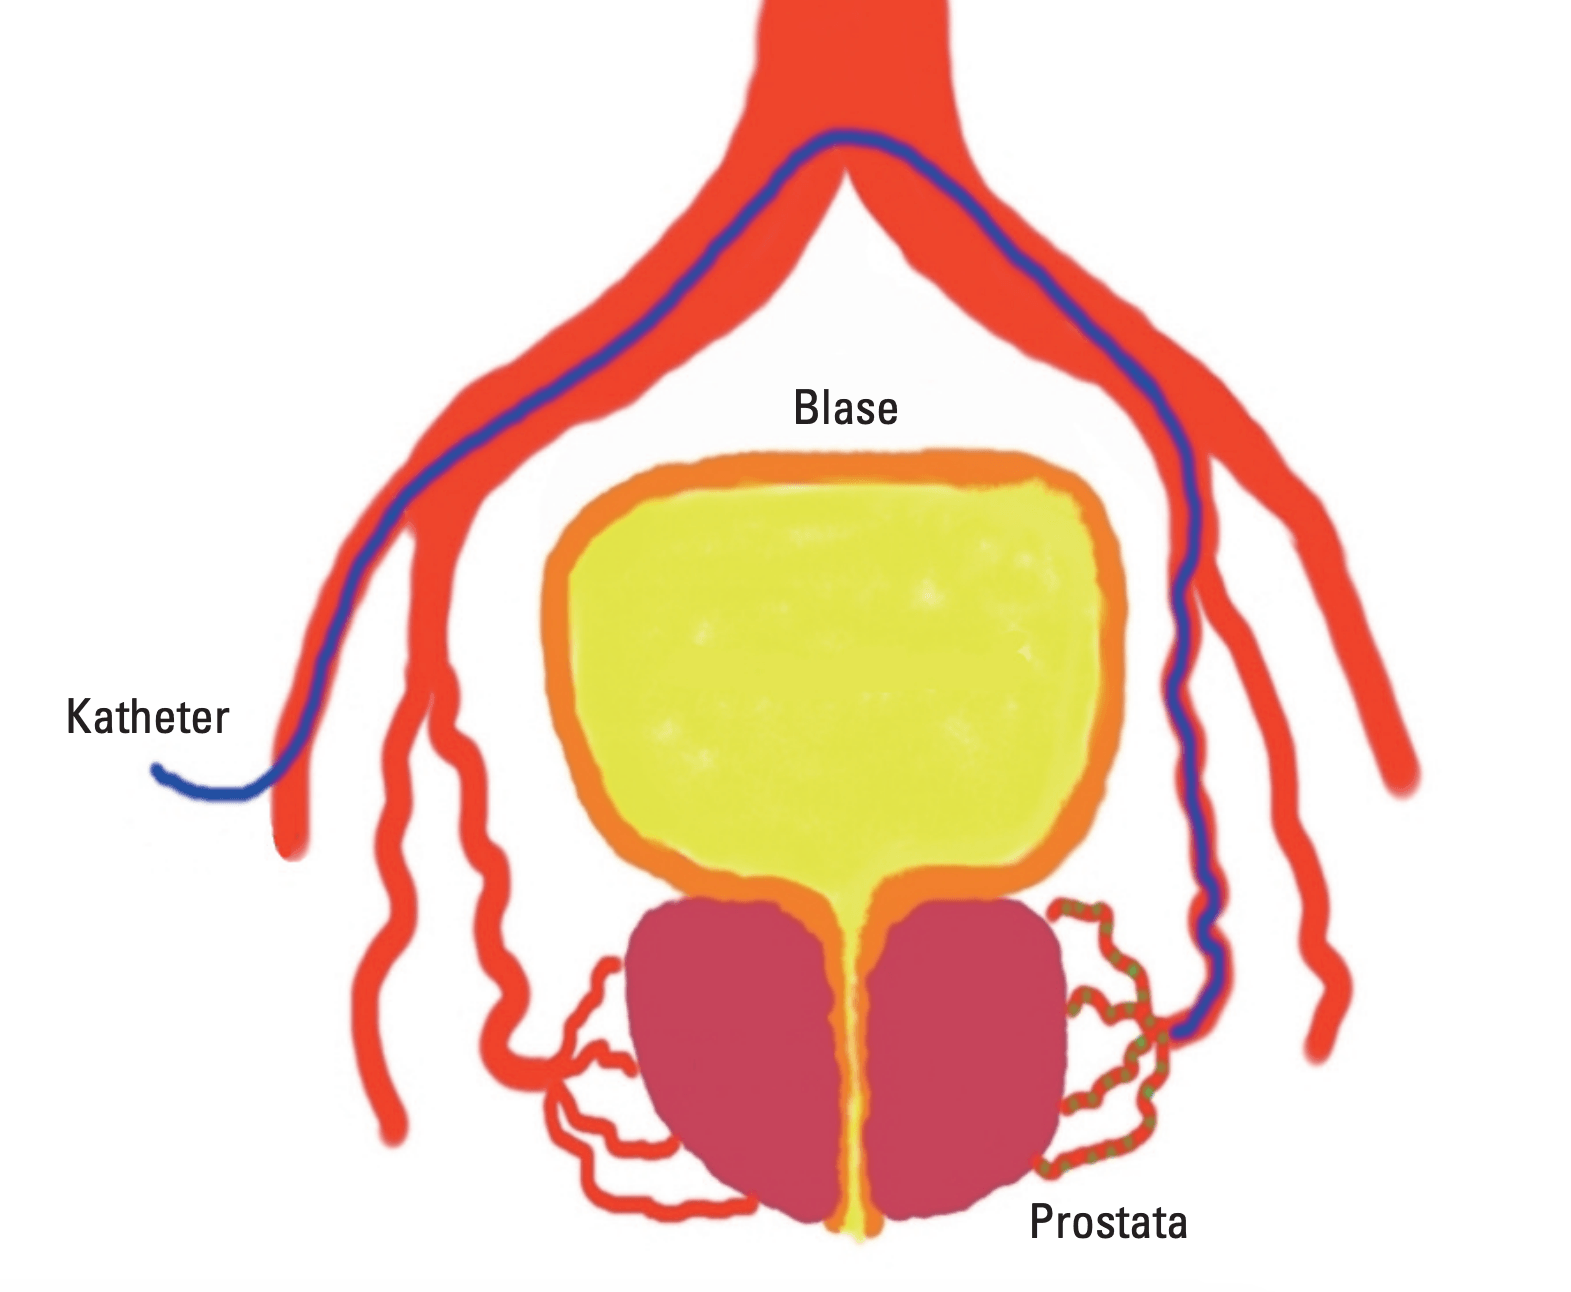

What modern technical equipment does the hospital include?

Among the leading technical equipment: are a gamma scalpel and a DaVinci robot. GammaKnife is an ultra-modern radiosurgical device that successfully treats tumors without open surgery. At the same time, DaVinci is designed to perform complex operations minimally-invasively.